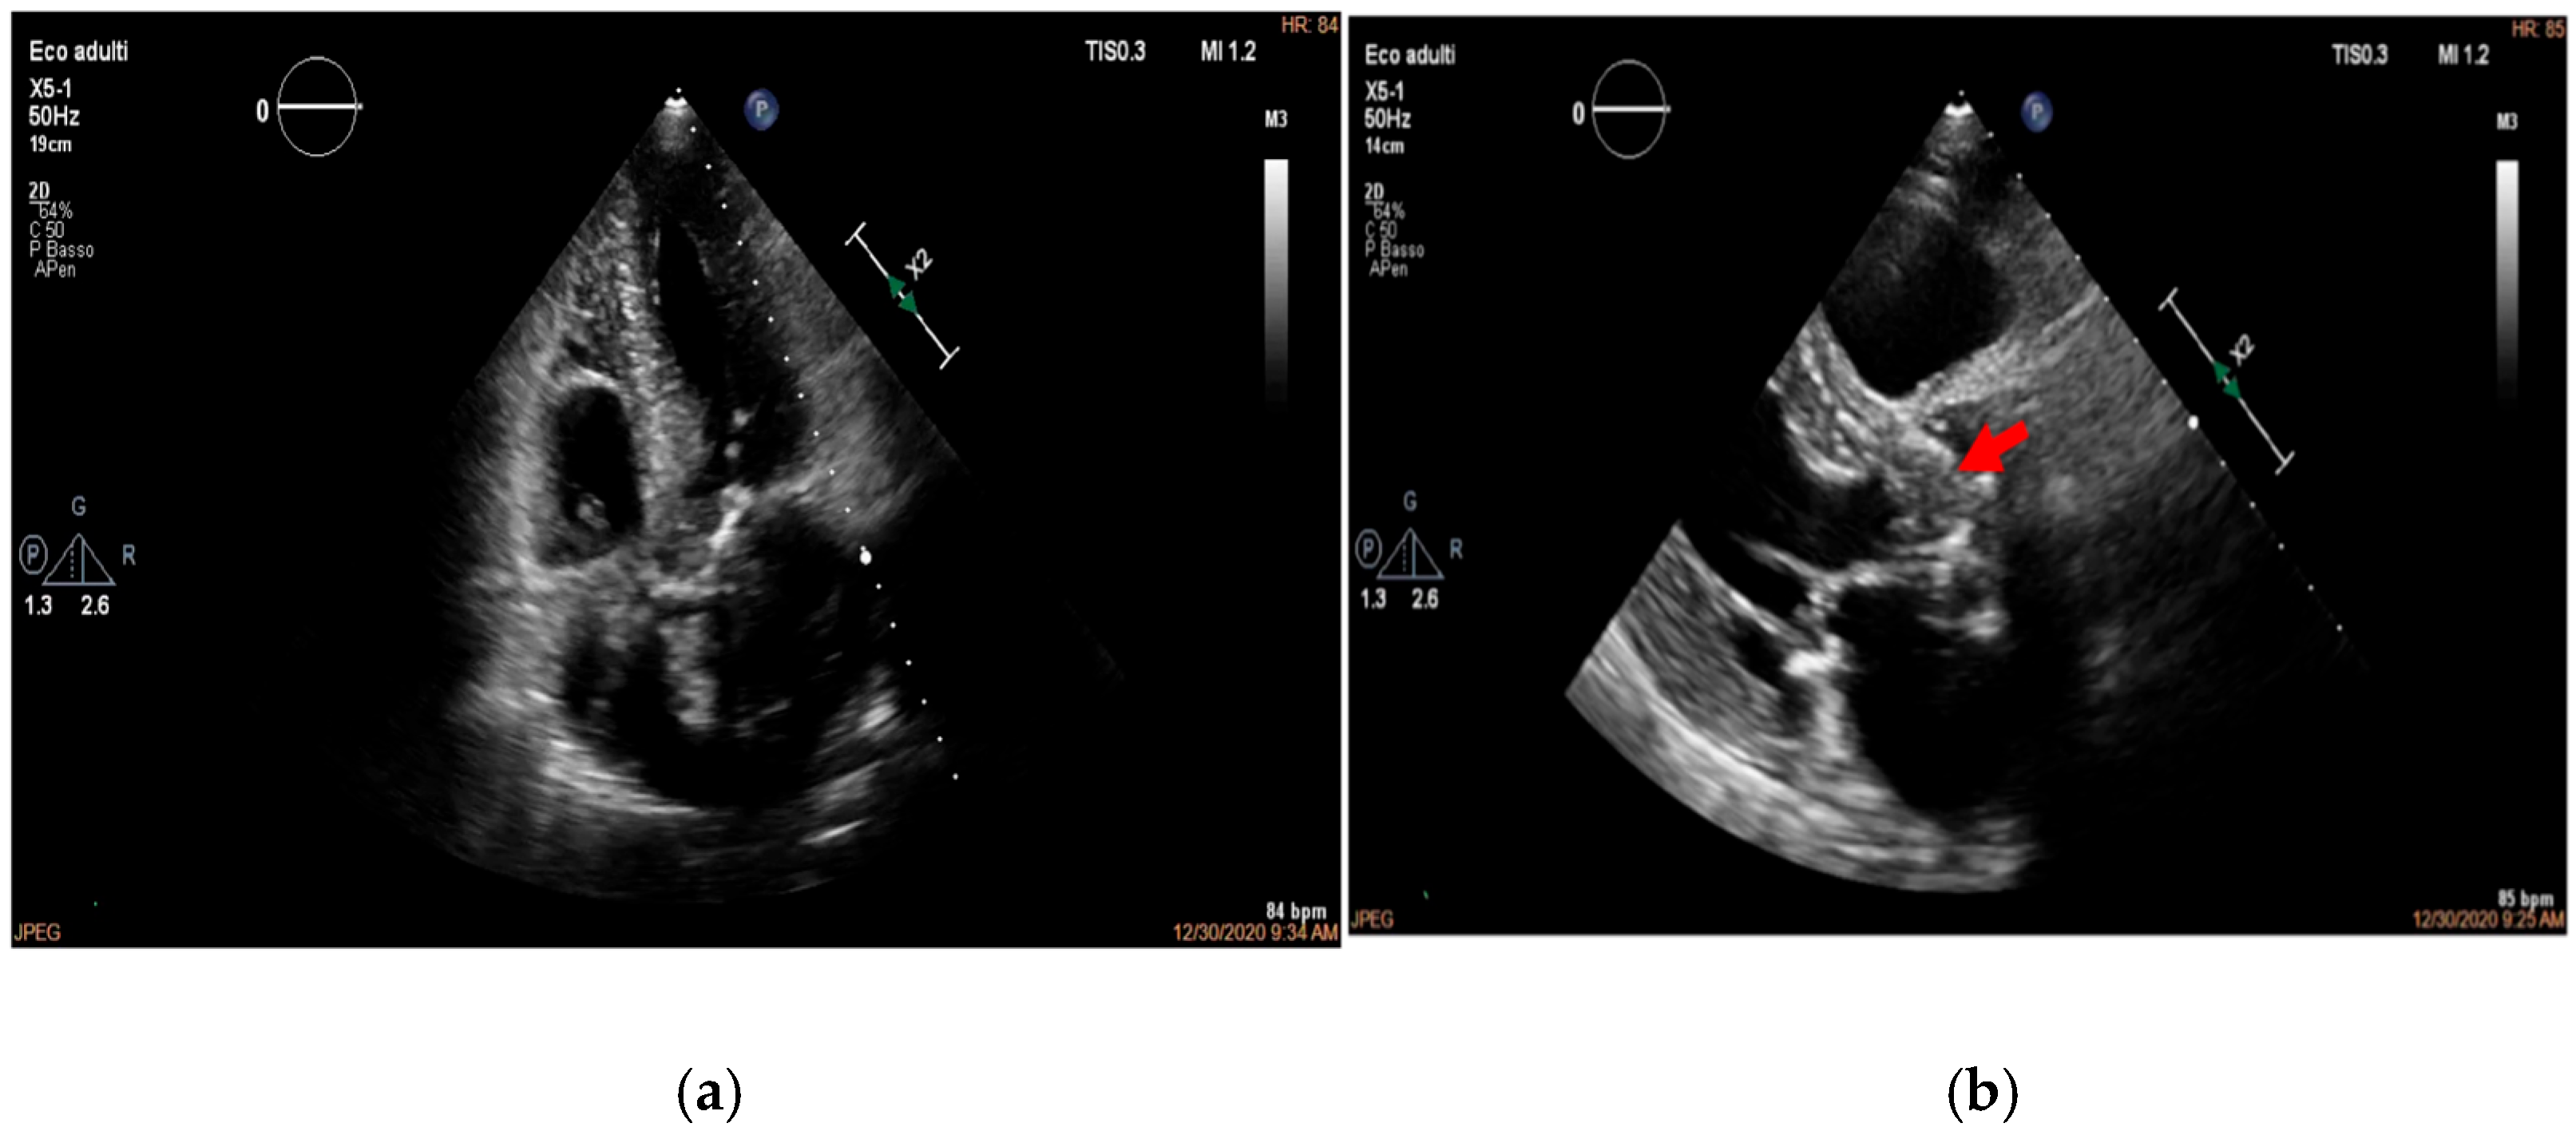

- valvular or leaflet perforation, i.e., tissue defects causing valvular regurgitation originating from the site of perforation.

- valvular aneurysm, a saccular outpouching of a valve leaflet, protruding into the atrium or ventricle.

- perivalvular or perigraft abscess, an echolucent or echodense area adjacent to the valve annulus or prosthetic ring often with irregular borders and sometimes with evidence of cavity formation.

- pseudoaneurysm, a contrast-filled outpouching with a narrow neck communicating with the cardiac lumen, often adjacent to the valve annulus. On echocardiography, it appears as a pulsatile cavity with systolic expansion and diastolic collapse.

- intracardiac fistula, visualized as an abnormal communication between cardiac chambers or vessels, is often detected by using color Doppler.

- significant new valvular regurgitation compared with previous imaging, i.e., increase in regurgitant jet size, vena contracta width…